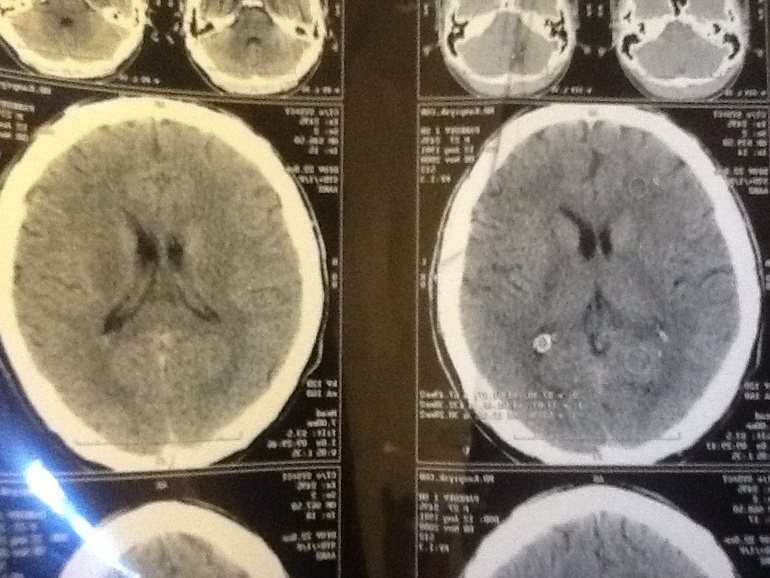

Здравствуйте. Не так давно я узнал что у меня опухоль мозга и на операцию нужны деньги. Я смог собрать лишь маленькую часть из того что нужно. Если есть возможность прошу помогите, даже 10 рублей сделают не мало если многие откликнуться. Прошу отправьте на номер телефона или карту сбербанка всего 10 рублей Пожалуйста! 8.916.812.35.18. Или на карту 4276 3800 1078 1917. Пожалуйста не судите и поймите правильно мне больше не куда обратиться

Здравствуйте. Не так давно я узнал что у меня опухоль мозга и на операцию нужны деньги. Я смог собрать лишь маленькую часть из того что нужно. Если есть возможность прошу помогите, даже 10 рублей сделают не мало если многие откликнуться. Прошу отправьте на номер телефона или карту сбербанка всего 10 рублей Пожалуйста! 8.916.812.35.18. Или на карту 4276 3800 1078 1917. Пожалуйста не судите и поймите правильно мне больше не куда обратиться